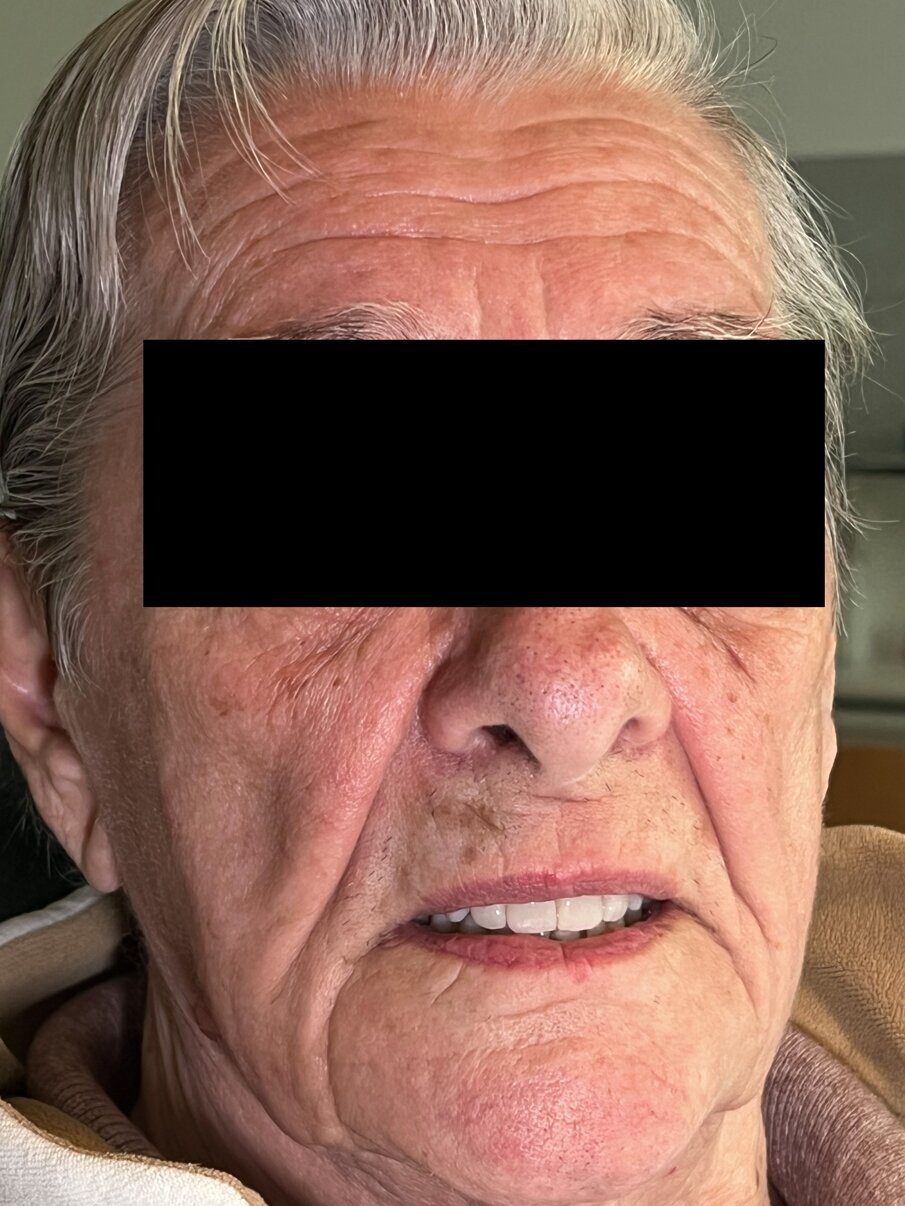

Paziente femmina di 75 anni in buona salute psico-fisica. Presenta una riabilitazione su impianti nell’arcata superiore con diffusa perimplantite e sindrome della bocca urente. Nell’arcata inferiore presenta protesi totale completa con denti abrasi e incongruenza tra le basi e i processi alveolari (Figg. 1-13).

Fig. 1_Volto in prima visita.

Fig. 11_La protesi inserita e ribasata all’arcata superiore.

Fig. 12_Controllo a 4 settimane.

Fig. 13_Controllo a 4 settimane: dettaglio della morfologia e texture del gruppo frontale.